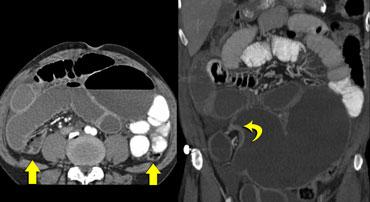

Tái tạo ảnh mặt phẳng coronal có thể rất hữu ích trong việc thể hiện toàn cảnh tổn thương.

Bên trái, chúng ta thấy đại tràng lên và đại tràng xuống không giãn (mũi tên thẳng) và điểm chuyển tiếp của xoắn (mũi tên cong).

Bên trái là hình ảnh điển hình của xoắn manh tràng.

Chúng ta có thể thấy vùng chuyển tiếp hình mỏ chim nằm ở góc phần tư dưới bên phải, cho thấy đây là xoắn manh tràng.

Manh tràng giãn nằm ở góc phần tư trên bên trái.

Cũng lưu ý đại tràng xuống xẹp nằm phía sau manh tràng giãn (mũi tên cong).